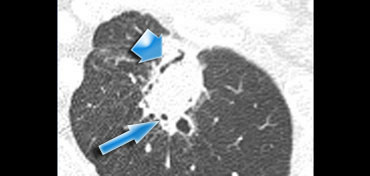

Air bronchogram sign seen in Air bronchogram sign seen in

Air Bronchogram sign

Recent studies have showed that an air bronchogram is more commonly seen in malignant pulmonary nodules.

It is most commonly seen in BAC (bronchoalveolar cell carcinoma) and adenocarcinoma.

The case on the left shows an airbronchogram seen as a linear lucency (broad arrow) and as a more cystic lucency (small arrow) due to the fact that the bronchus is seen en face.